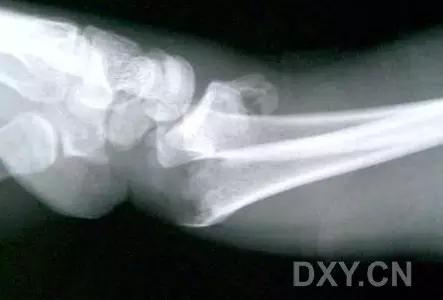

9. Essex-Lopresti 骨折

是桡骨头骨折伴有下尺桡关节脱位,导致骨间膜损伤,桡骨短缩。此种损伤,桡骨头骨折的诊断往往是明确的,容易忽视的是下尺桡关节脱位,特别是早期,下尺桡关节的症状不明显,X 线表示也不明显。

Essex-Lopresti 损伤。前后位(A)和侧位(B)示桡骨头关节内骨折(白色实线箭头);(C~E)伤后 1 个月复诊,患者诉腕关节疼痛,X 线(C,D)发现下尺桡关节脱位,(E)CT 进一步证实损伤的存在 (来源:Radiol Clin North Am. 2015 Jul;53(4):717-36)